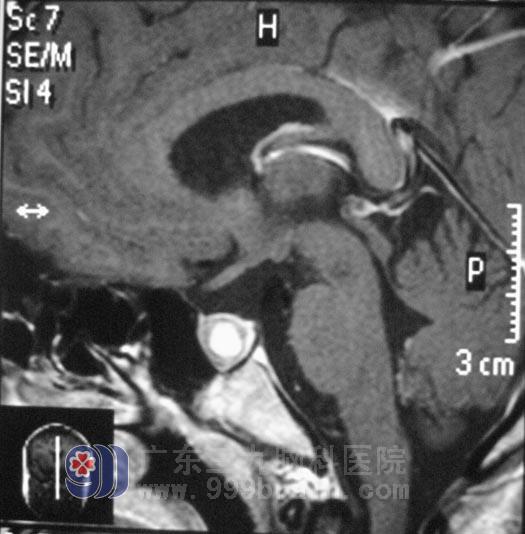

广东三九脑科医院垂体瘤诊疗中心鲁明主任给她检查脑部的MRI发现:鞍区占位,考虑垂体瘤卒中。内分泌检查提示泌乳素250ug/L(正常1.9-25ug/L)。鲁明主任告知:珠珠的闭经,正是 垂体瘤所致。

4月1日,珠珠在全麻下行“经鼻蝶鞍区占位切除术”,术中使用导航仪进行肿瘤定位,经过2个多小时,在显微镜下将肿瘤全切。术后经过专科监护,没有出现尿崩等不良并发症。住院一周左右,顺利出院。术后病理回报为:PRL表达型垂体腺瘤。

手术前